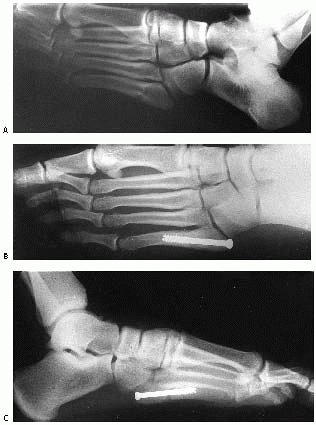

severe intra-articular fractures with displacement of the fragments and

outcome measures (Fig. 27-19).10,126,143,144,145,146

FIGURE 27-19 A. Lateral L-shaped approach to displaced intra-articular calcaneal fractures. The incision (dashed line)

is laterally based, with the proximal arm approximately half the distance from the fibula to the posterior border of the foot and the distal arm halfway from the tip of the fibula to the sole of the foot. The sural nerve is illustrated. A full-thickness, subperiosteal flap exposes the entire lateral calcaneus. B. Reduction maneuvers 1, 2, and 3 (densest arrow indicates greatest displacement) with a Schantz screw are used to pull the tuberosity down and allow access to disimpact the posterior facet (C) after the lateral wall of the calcaneus is levered open. The posterior facet is then reduced anatomically, held provisionally with K-wires, and then fixed with two partially threaded cancellous screws (outside of plate) into the sustentaculum tali. Lateral view (D) of reduced calcaneus and axial view (E) of reduced fracture with hardware. (From Benirschke SK, Sangeorzan BJ. Extraarticular fractures of the foot: surgical management of calcaneal fractures [Review]. Clin Orthop Relat Res 1993;292:128-134; with permission.) |

![]() |

FIGURE 27-20 Intra-articular depressed fracture of the calcaneus in a 13-year-old boy. A. Preoperative sagittal CT shows the depression of the posterior facet into the body of the calcaneus. B. Coronal CT shows the displacement of the frature fragments. C. Postoperative CT scans are useful at checking the fracture reduction and length and position of the screws. D,E. Postoperative radiographs confirm restoration of the Böhler angle.

|